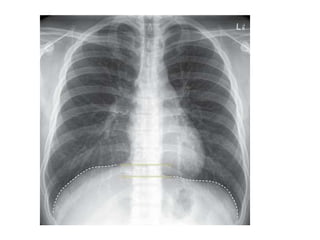

a. Inspiration

 The diaphragm should be found at about the

level of 9 - 10th posterior rib or 5 - 6th anterior rib

on good inspiration

Inspiration Expiration

Note Changes In Heart Size And Vascularity Due

To Expiration.